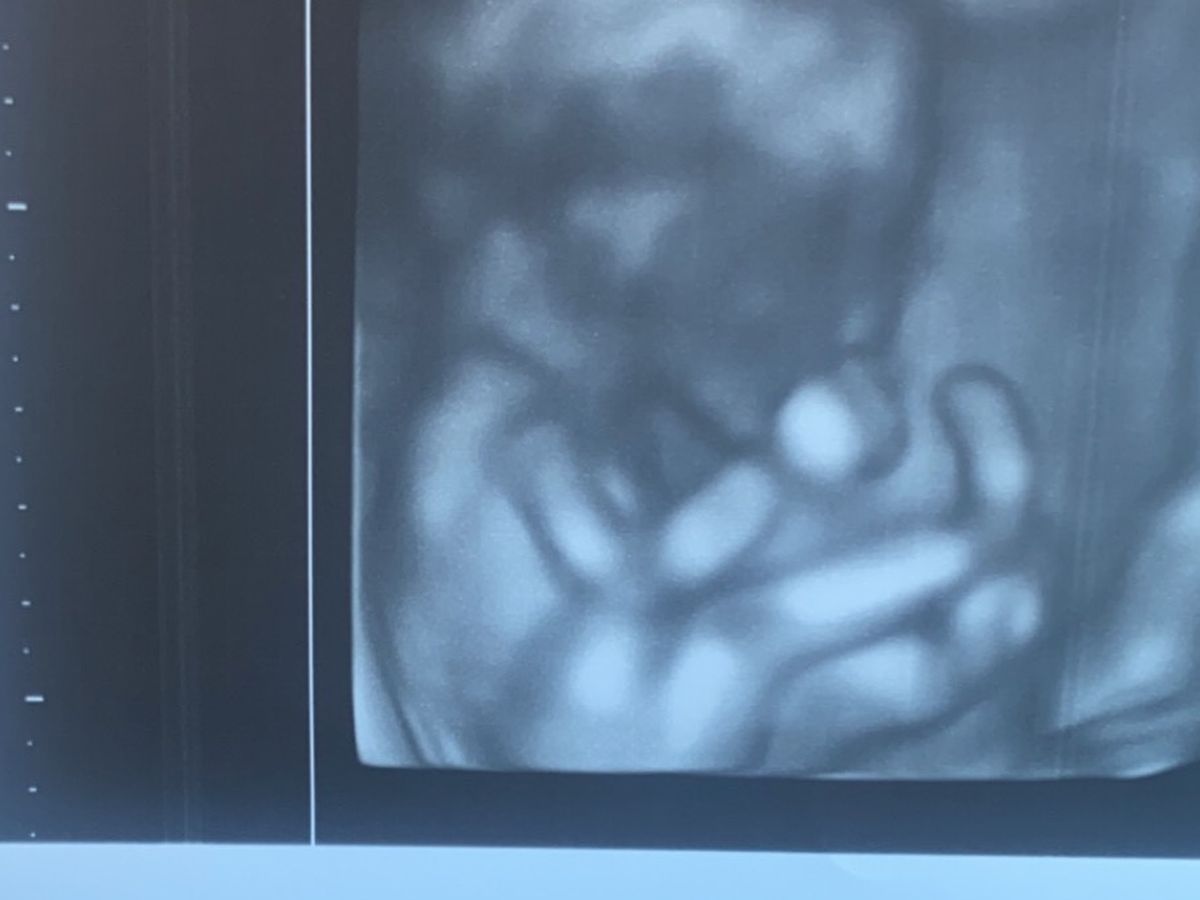

It is with a heavy and broken heart I have to announce that I will be induced to deliver Evalina tomorrow… due to my body being in a very unstable state because of my heart and kidneys and the preeclampsia i have developed.. my doctors have exhausted all options and unfortunately it is a matter of saving my life at this stage… due to evalinas severe IUGR and her gestational age she will not survive long after birth… I will be able to see and hold her for a bit but I would like to have a memorial for her and always have her with me. Any leftover expenses will go to bills and basic needs as I will not be able to go back to work for a while due to recovery and grieving. Thank you for all of your prayers